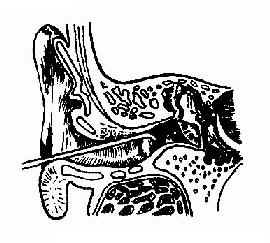

(二)植物性异物可在直视下用异物钩或耳刮匙取出,不宜用水冲洗,以免膨胀而取出困难(图11-1)。

| 图11-1 外耳道异物钩出法 | 图11-2 外耳道异物镊取法 |